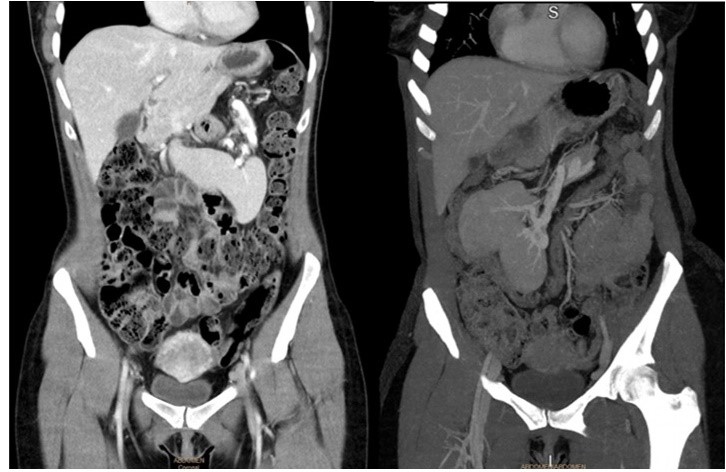

Mujer de 39 años, sin factores de riesgo cardiovascular y con asma ocasional en tratamiento con Symbicort®. No presentaba antecedentes quirúrgicos. Durante el embarazo se realizó una ecografía de rutina en la que se observó una masa abdominal sólida con eje vascular en hipogastrio compatible con el bazo. Posteriormente se completó el estudió con una tomografía computarizada (TC) abdominal con contraste, en la que se el bazo estaba en región epigástrica y presentaba una alteración de la morfología con rotación del hilio. El resto de la exploración era normal. La paciente refería en ocasiones sensación de masa abdominal que cambiaba de posición con los movimientos. Ante el hallazgo de bazo errante, se decidió cirugía. Se efectuó una nueva TC prequirúrgica, en la que se objetivó el bazo alojado en vacío derecho, con un pedículo vascular de trayecto descendente y oblicuo derecho, que arrastraba parcialmente la cola de páncreas (ver imagen 1).

Imagen 1: TC abdominal con contraste (izquierda) en 2018 con bazo en epigastrio con rotación del hilio esplénico. TC abdominal con contraste (derecha) en 2020, con bazo en vacío derecho.